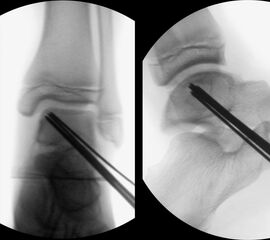

Behandlungsziel ist die exakte Rekonstruktion der Gelenkfläche sowie die Minimierung des Risikos einer späteren Wachstumsstörung. Dislozierte Frakturen werden offen reponiert, die Osteosynthese erfolgt mit einer Kleinfragmentschraube. Finden sich viele kleine Fragmente kann eine K-Draht Osteosynthese durchgeführt werden. Wird der Innenknöchel operiert, kann bei gleichzeitiger hochgradiger lateraler Instabilität eine Rekonstruktion des lateralen Bandapparats durchgeführt werden. Fibula Frakturen stellen sich meist spontan ein, sodass hier keine zusätzliche Osteosynthese notwendig ist.

Nach der Osteosynthese wird die Fraktur für ca. vier Wochen in einem Unterschenkelgips ruhiggestellt. Bei Schmerzfreiheit der Frakturzone erfolgt anschließend eine schmerzadaptierte Belastungssteigerung über weitere zwei Wochen. Sobald unter Alltagsbedingungen Beschwerdefreiheit besteht kann die sportliche Belastung langsam gesteigert werden. Kirschnerdrähte werden 6-8 Wochen postoperativ, Schrauben nach zwölf Wochen entfernt. Es empfiehlt sich klinische und radiologische Kontrollen im Abstand von 6 Monaten bis zum Wachstumsabschluss durchzuführen, um ein mögliches Fehlwachstum frühzeitig zu erkennen.